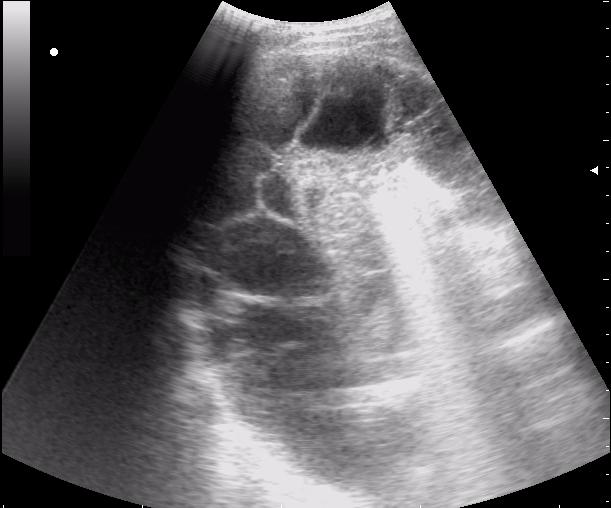

сегментарная пневмония. Экссудативный плеврит.

30790.JPG